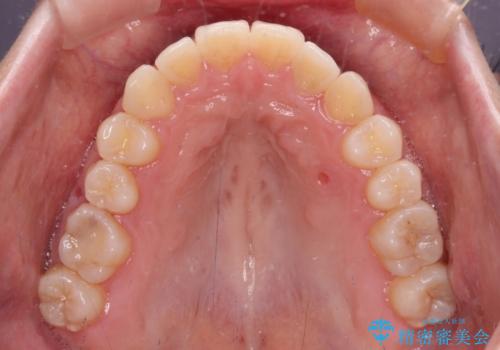

狭い歯列を拡大 拡大装置を併用したインビザライン矯正

インビザラインによる矯正治療を希望されたため、上顎歯列の側方拡大奥歯の遠心移動のための補助装置を併用し、その後はインビザラインにて行うこととしました。